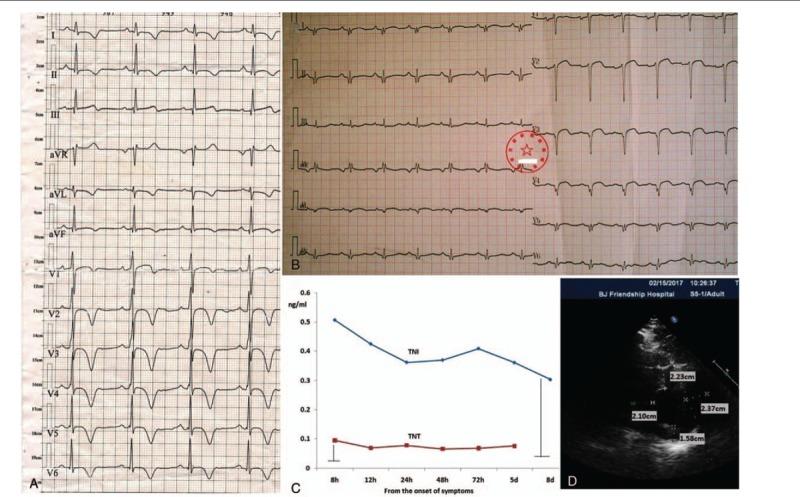

A 33-year-old man who presented with chest discomfort for 10 days. He had an emerging apical aneurysm in the LV without midventricular obstruction. He had been diagnosed with apical HCM via abnormal electrocardiograms (ECG) and single-photon emission computed tomography (SPECT) for 10 years. This time, a new significant change in ECG and SPECT was identified. Late gadolinium enhancement (LGE) was observed by cardiac magnetic resonance imaging (MRI), and SPECT showed myocardial fibrosis or necrosis involving the apical aneurysm and proximal portion of the heart, which was confirmed by left ventriculography.

一名33岁男性,因胸部不适10天前来就诊。他左心室出现了一个新的心尖部动脉瘤,无室中隔梗阻。他通过异常心电图(ECG)和单光子发射计算机断层扫描(SPECT)被诊断为心尖部HCM已有10年。此次,ECG和SPECT出现了新的显著变化。心脏磁共振成像(MRI)观察到晚期钆增强(LGE),SPECT显示心肌纤维化或坏死累及心尖部动脉瘤及心脏近端部分,左心室造影证实了这一点。